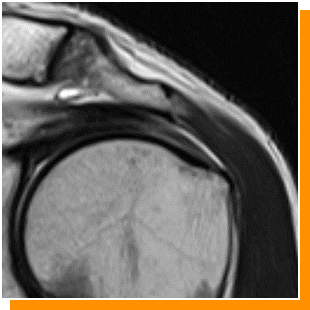

症例 3